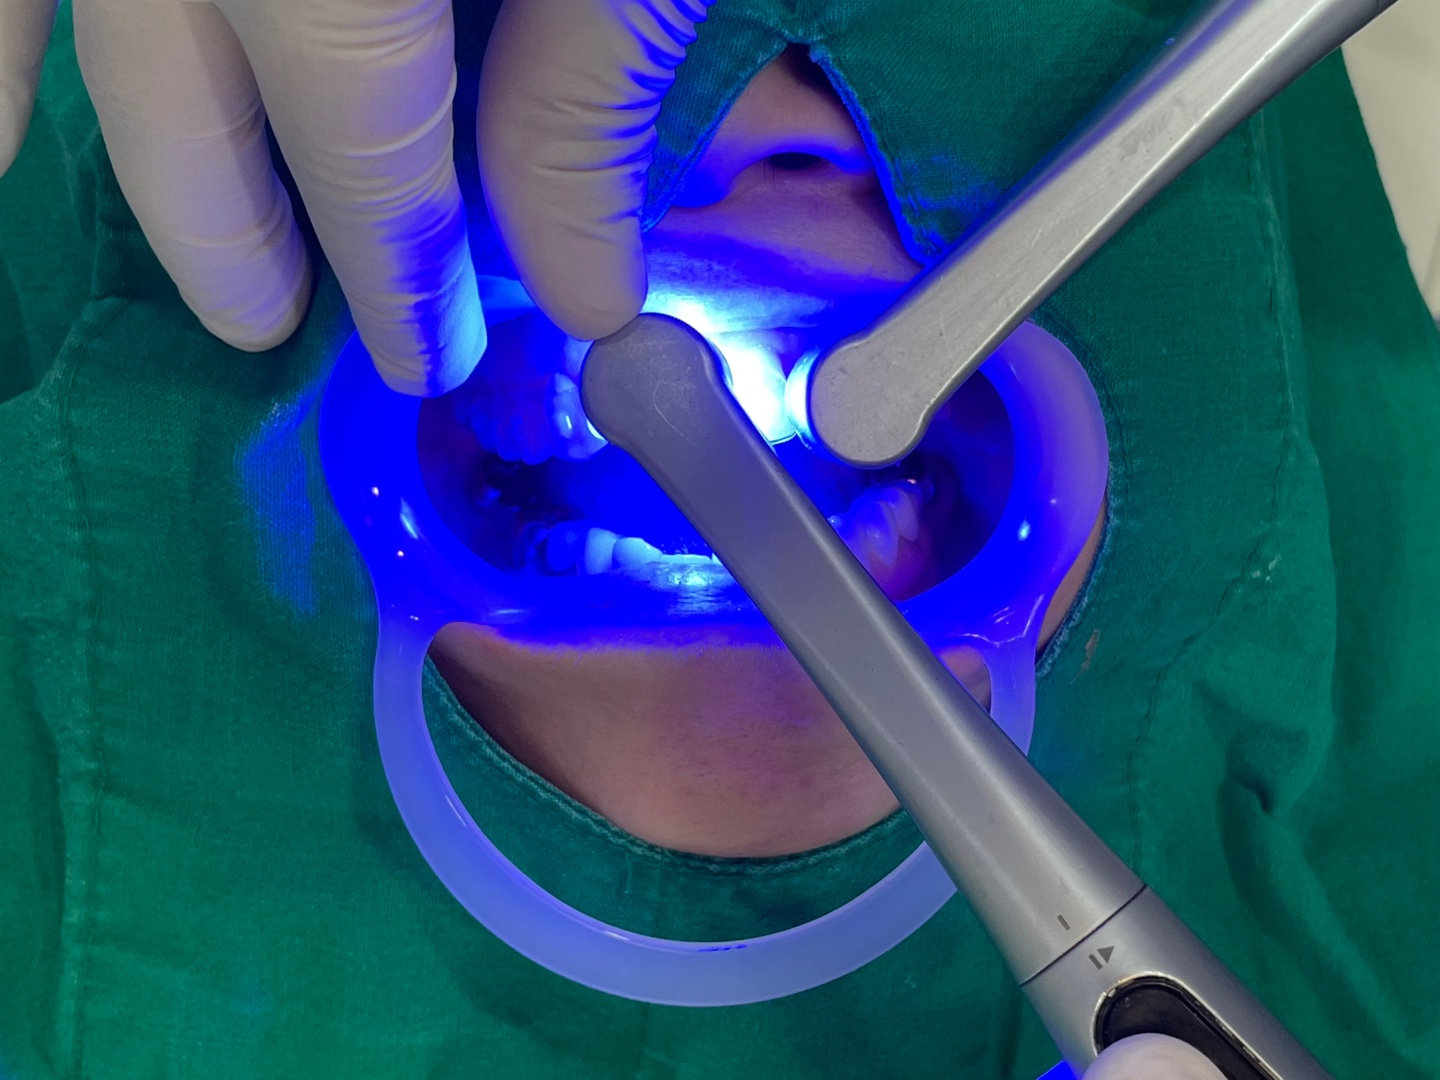

첫날 상당히 긴 시간동안 환자분이 협조해 주셔서

첫 단추를 잘 채웠습니다.